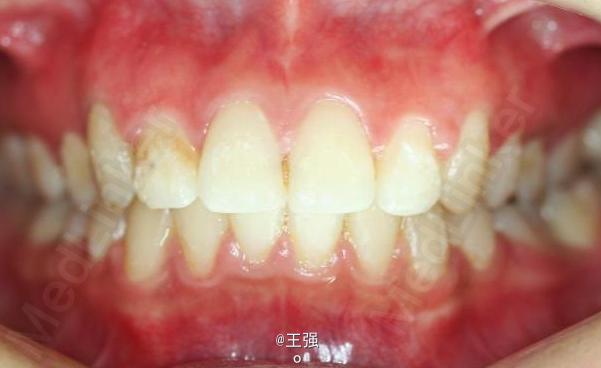

又一例不对称拔牙

牙弓狭窄,牙列拥挤

不对称拔牙